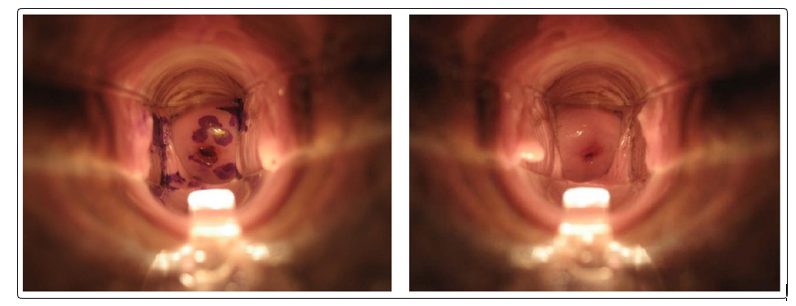

None of the participants reported any significant side effects using either device. Naked eye examination did not show any significant lesions over the cervix or the vagina. Women did not report any leakage while wearing the FemCap and the photograph of their cervix shows the presence of the stain over the cervix 24 hours after insertion (Figure 4). Women who used the vaginal applicator reported increased leakage of the stained lubricant and the photograph shows the absence of the stain 12 hours after insertion (Figure 5).

Figure 4: FemCap 24hr after insertion Figure 5: Vaginal Applicator 12hr after insertion